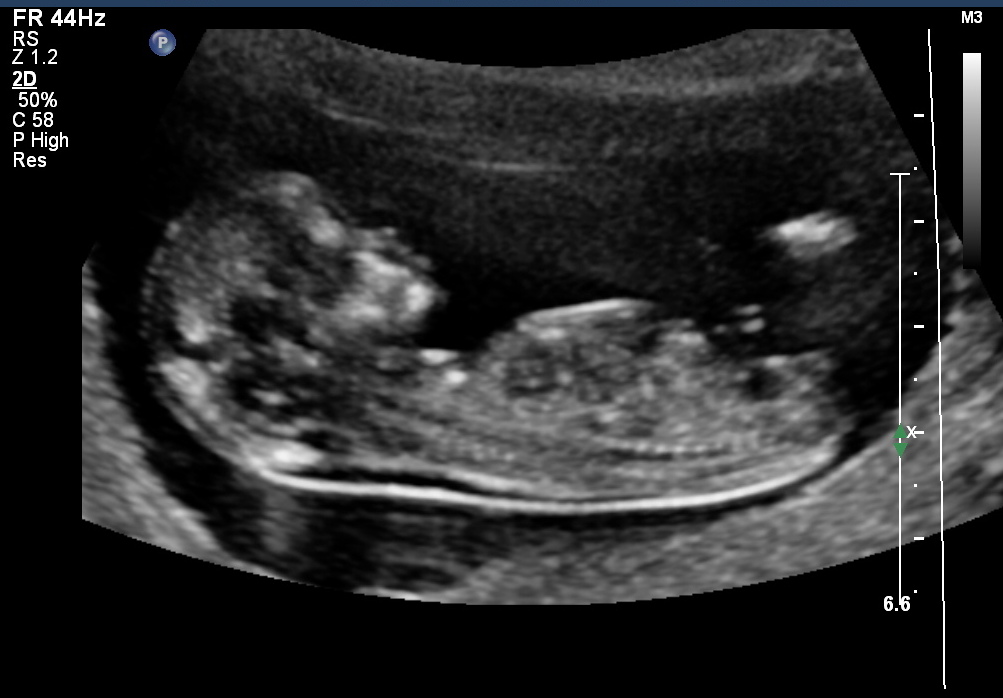

HI i had my scan done at 12 weeks and 1 day(very accurate as i had previous scans) but this bub must of had a growth spurt as it measured 13 weeks on the day. Any ideas of the gender? Would it be more accurate as bub measured 13 weeks?? thanks!!

Very convincing for a GIRL!!!

I was thinking girl but was wondering if it was stretching back to make the nub point straight. Hopefully not

Hi bub2 have a lookat my nub shot looks similar I thinK I am leaning more boy or you tho. There is angle and it doesn't look flat

I'd put money on this being a girl

Wow it does look like yours baby2ontheway! Is urs a confirmed boy?

When was ur scan done? I have a little boy so a girl

Would be lovely but will be wrapped with a boy

I dreamt it was a boy so I'm pretty convinced!

Can anyone pick what the gender is from the skull?